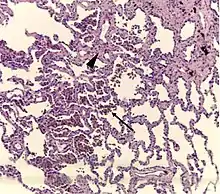

| A "smoker's macrophage", with yellow to light brown and finely granular cytoplasmic pigment. | |

- Pathologic: Lung biopsy with "smoker's macrophages" limited to distal airspaces and peribronchiolar airspaces, and minimal to absent peribronchiolar interstitial fibrotic thickening